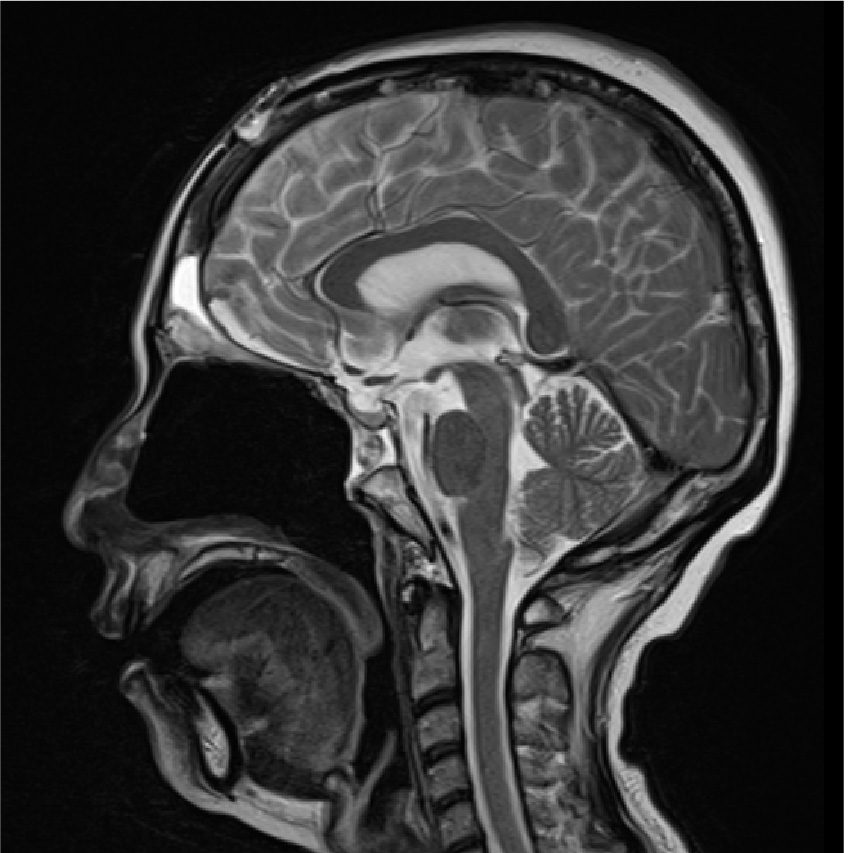

外視鏡と内視鏡を組み合わせて治療した腫瘍のMRI画像です。

髄膜腫:小脳、脳幹、聴神経などが圧迫されている

術前MRI

術後MRI